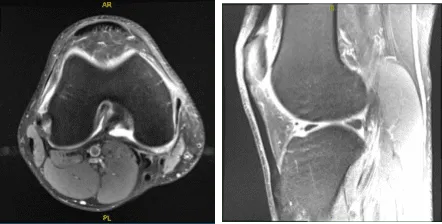

Se revisaron y comentaron las resonancias magnéticas durante la visita. Los resultados han mostrado una compleja rotura del menisco medial y un esguince reactivo del ligamento colateral medial. Derrame articular muy pequeño.

MRI-3T Rodilla derecha sin contraste